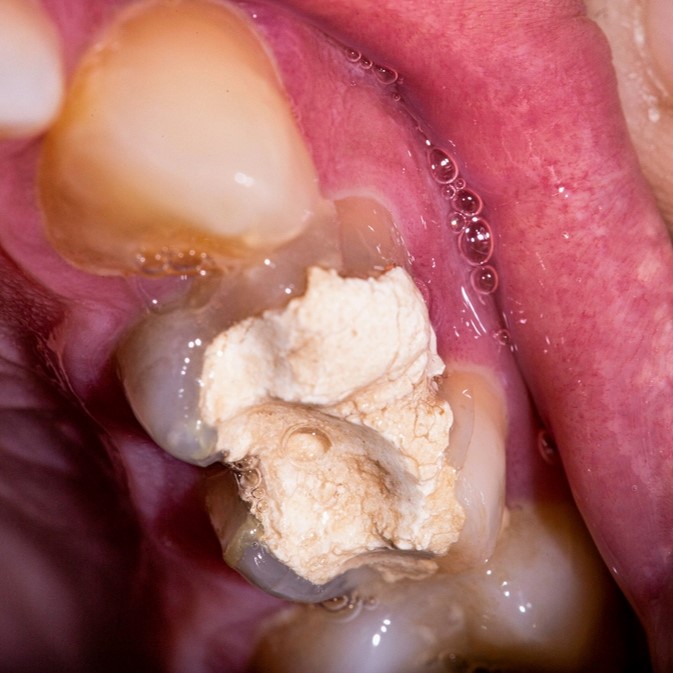

More dental schools (83%) taught indirect pulp therapy (IPT) compared to 1997. Significantly more used glass ionomer for IPT with most dental schools and diplomates not re-entering a tooth after IPT. Over 30% of schools and diplomates do direct pulp caps using glass ionomer. For pulpotomy, diluted formocresol usage decreased in dental schools (54%) while ferric sulfate significantly increased (24%) and full strength remained at 22%. Shorter placement of pulpotomy medication was noted and ZOE alone the preferred base. Pulpectomy was advocated by 85% of 2005 schools and diplomates with ZOE filler use decreasing while iodoform/calcium hydroxide filler use increasing.

More pediatric dentists are using glass ionomer for IPT and direct pulp capping, and there was a trend away from the use of 1:5 diluted formocresol with more using ferric sulfate for pulpotomy. For pulpectomy, most use ZOE but iodoform pastes and calcium hydroxide have increased in usage since 1997. Disagreements continue concerning when to use certain pulp therapies and some directors and diplomates did not follow the AAPD guidelines.